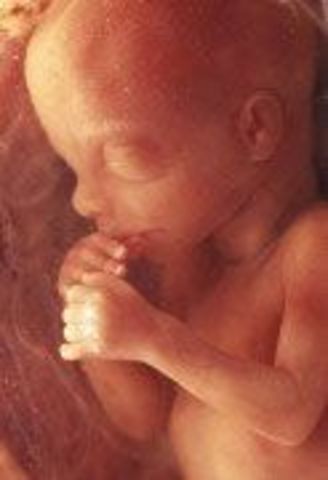

• Week 9: Fingers and Toes Form

Week 9: Fingers and Toes Form

Many more body parts are forming such as the tongue, the bones, eyelids, etc. The fingers and toes are the most defined. The baby is developing in a little bag of fluid which it is swimming around in.

• Week 10: Embryo is Now a Fetus

Week 10: Embryo is Now a Fetus

The embryo is now called a fetus until birth. The fetus is the size of a small strawberry. The fingerprints are becoming evident in the skin and the nipples and hair follicles are forming as well.